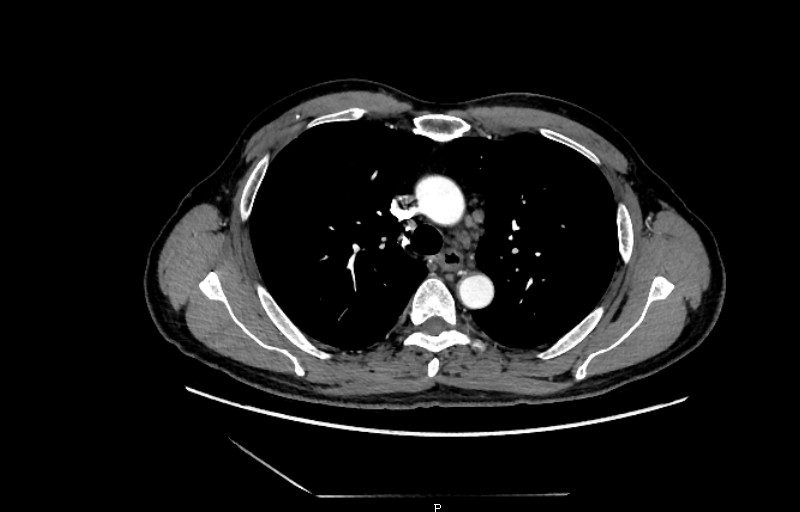

为稳妥起见,张涛教授给他做了6处活检,同时安排做了胸部+腹部ct平扫及增强,初步结果提示:1、食管管壁增厚,食管癌并纵隔及右肺门淋巴结转移?请结合内镜检查及临床资料;2、两肺散在结节,炎性结节?转移?请密切随诊;3、右肺第6肋骨腋段高密度影,骨岛?其他?4、肝S8段囊肿;5、右肾复杂性囊肿;6、前列腺增生。